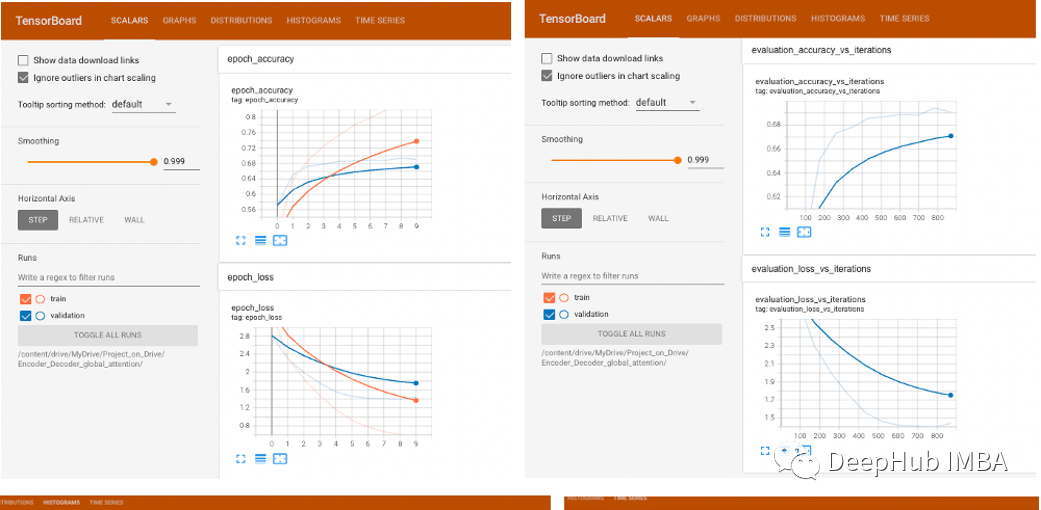

模型训练了10轮,可以看到损失为0.5577,精度为0.8466,验证损失和精度分别为1.4386和0.6907,如果我们继续运行模型,可以得到更好的损失和精度,但看起来模型是过拟合的,因为得到了10轮的最佳结果。

可视化可以看到,评估精度随着迭代次数的增加而增加,评估损失随着迭代次数的增加而减少,这是一个很好的迹象,表明权重正在收敛,所有导数都在良好的范围内,没有爆炸或消失的梯度。